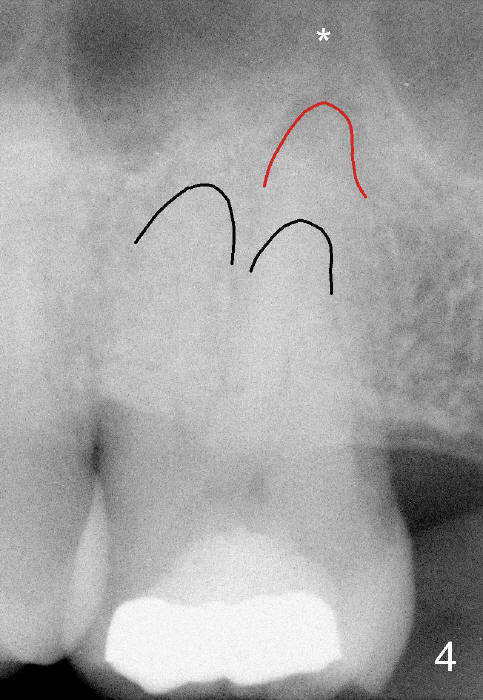

A 52-year-old black man fails to return to finish root canal therapy for the tooth #15; ultimately it is non-salvageable (Fig.1-3). The tooth has 3 basically fused roots (Fig.4 black (buccal) and red (palatal) outlines), above which is the sinus septum (*). By inserting an immediate implant into the sinus septum, primary stability should be high (Fig.5 vs. 6).